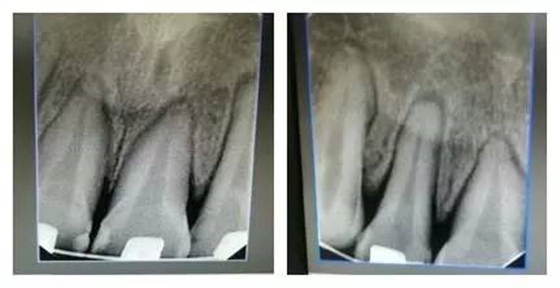

每一位臨床醫(yī)生每天都會面臨各種困惑和難題,只要我們堅持思考,善于溝通、勤于實踐,(牙合)學的神秘大門將會為我們敞開。這是權老師最初在(牙合)學群里分享的一句話。最近,權老師在(牙合)學群里分享自己的病例,“堅持思考,善于溝通、勤于實踐”,她不僅用這樣的話激勵群里的每一位同仁,更一直在行動著。讀讀病例,讓我們開始思考…… 病例:患者,女,22歲。 主訴:8年前曾行正畸矯正,現(xiàn)因美觀及功能需求,要求重新矯治。 現(xiàn)病史:2個月前,開始戴用矯治器,以0.012Niti初始絲,近2個月來無明顯不適。2天前,上前牙開始出現(xiàn)咬硬物疼痛,冷熱刺激痛,自覺松動。 檢查:上前牙松(Ⅱ)°,牙齦紅腫,牙周膜間隙增寬。(如照片所示)

由上圖可知,患者全口牙齒磨耗較重,尖牙牙尖磨耗,無法起到引導和保護作用,上前牙牙根短,上中切牙腭側面邊緣嵴消失,

由此推斷:尖牙牙尖磨耗,患者在前伸(牙合)運動時,引導不足,前牙的接觸面過大,受力較大;患者在側方(牙合)運動時下前牙沒有了引導,會直接對側切牙造成撞擊;再加上前牙根較短,無法耐受,引起(牙合)創(chuàng)傷,繼發(fā)牙髓癥狀;失去尖牙保護(牙合),加重了牙齒的磨耗。